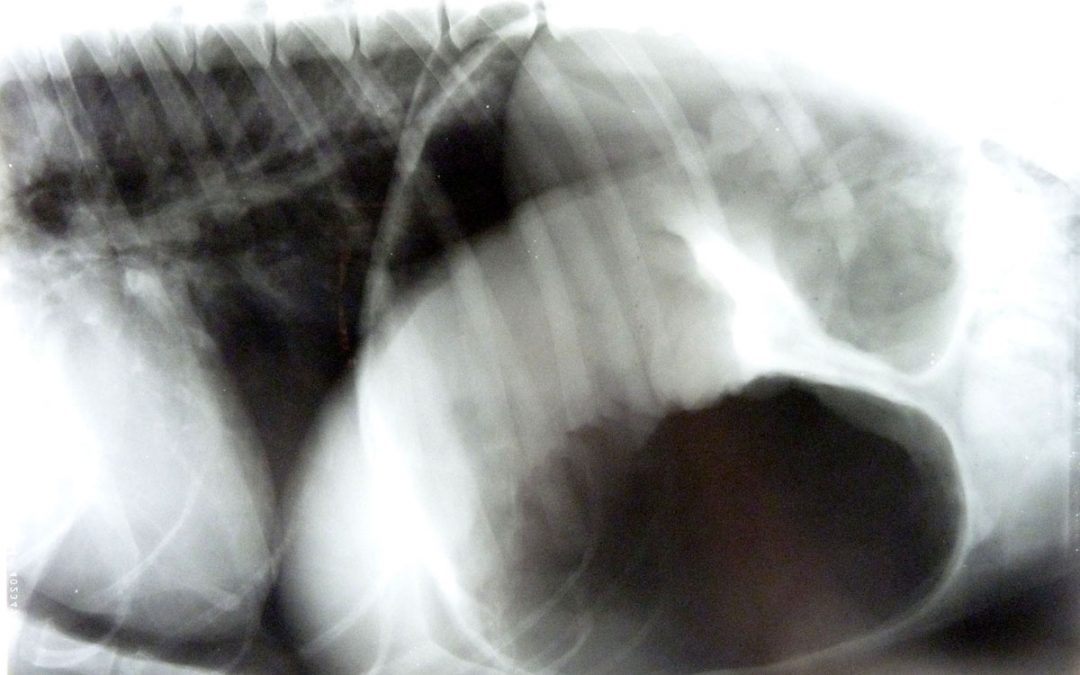

Cila bekam sofort einen Venenzugang gelegt und eine Infusion mit Schmerzmittel und kreislaufstützenden Medikamenten. Der Magen wurde an seiner höchsten Position mit etlichen Kanülen punktiert um erst mal die Luft abzulassen. Es wurde ein Röntgenbild angefertigt. Das Röntgenbild zeigte die massive Aufgasung des Magens mit der typischen Einziehung (“Falte”) die durch das sich einklemmende Milz-Nierenband entsteht. Es handelte sich also wirklich um eine Magentorsion und nicht bloss um eine Magenaufgasung .Der Herzschatten und das Abhören des Herzens waren zu dem Zeitpunkt ohne besonderen Befund.